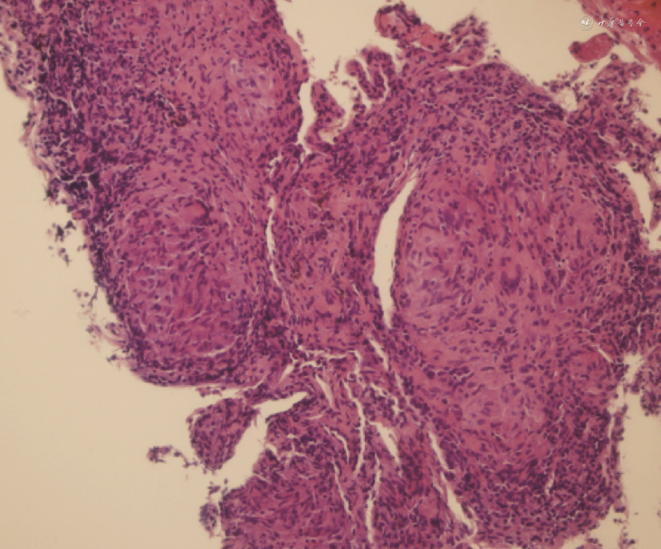

入院后查血常规:淋巴细胞计数1.057×109/L(正常参考值1.10~3.20×109/L),余正常;九项呼吸道感染病原体IgM抗体:抗肺炎支原体IgM抗体(+);肿瘤标志物:神经元特异性烯醇化酶(NSE)36.20 μg/L(正常参考值≤20.0 μg/L);抗核抗体谱:抗SSA抗体(+++),抗Ro-52抗体(+++);抗核抗体:核颗粒型1∶320(+)。大小便常规、肝肾功能、静脉血葡萄糖、电解质、凝血功能、细胞免疫功能、感染性疾病筛查均正常。血清(1,3)-β-D葡聚糖(G试验)、半乳甘露聚糖(GM试验)、抗中性粒细胞胞质抗体(ANCA)以及诱导痰细菌和真菌涂片及培养、抗酸杆菌涂片均为阴性。新型冠状病毒核酸阴性。床旁心电图:窦性心律,正常心电图。胸部CT:双肺多发大小不等斑片影,中央为磨玻璃密度影,边缘为环状高密度影,呈反晕征;病灶内可见多发微结节堆积,呈结节状反晕征(图1, 2, 3, 4, 5, 6)。支气管镜检查:支气管黏膜呈炎症表现,气管腔内可见少许白色泡沫痰,未见狭窄及新生物。双上肺BALF送检细菌和真菌培养、涂片查抗酸杆菌、分枝杆菌核酸(TB/NTM-DNA)和Xpert MTB/RIF均为阴性;BALF液基制片:未查见癌瘤细胞。于右上叶后段行黏膜活检术,病理示黏膜慢性炎症。(2023年2月22日)行CT引导下左上肺病灶穿刺活检术,病理示慢性肉芽肿性炎(图7),未查见抗酸杆菌。患者有口干症状,抗SSA抗体、抗Ro-52抗体强阳性,考虑干燥综合征可能,给予完善唇腺活检,病理示:送检唇腺内查见淋巴组织浸润>1灶,活检分级为Ⅳ级。患者干燥综合征诊断明确,但双肺多发反晕征是由活动性肺结核还是干燥综合征继发机化性肺炎(OP)导致仍不能确定。多学科诊疗团队(MDT)讨论后认为:患者青年男性,免疫功能正常,肺部病变以双上肺分布为主,表现为多发反晕征伴微结节堆积,与典型OP环壁光滑的反晕征不符,且TSPOT.TB呈阳性,病理见肉芽肿形成,高度怀疑为活动性肺结核;但结节病、干燥综合征继发的其他肺损害亦不能完全排除,建议病理组织完善结核分枝杆菌聚合酶链反应(TB-PCR)检测,必要时在征得患方同意后可予诊断性抗结核治疗。(2023年3月1日)病理组织外送TB-PCR(成都中医药大学附属医院):TB-DNA(+)。最终诊断:活动性肺结核合并干燥综合征。因患者无多系统受累表现,故仅给予标准四联方案抗结核治疗,未使用糖皮质激素或免疫抑制剂,嘱其至传染病医院及风湿免疫科门诊随诊。1个月后电话随访患者,诉其正接受抗结核治疗。遗憾的是,目前未能与患者取得再次联系,故未能知晓其治疗转归。

结节状反晕征(nodular reverse halo sign,NRHS)是反晕征中相对特殊的类型,即在反晕征的环壁和(或)环内出现了弥漫分布的微结节,这些微结节在组织学上与肉芽肿相对应[3]。国内学者亦将这种成簇状堆积的小叶中心性微结节命名为“烟花征(fireworks sign)”,并根据局部堆积的微结节数量差异将烟花征分成了晕征样、反晕征样和均匀样3种不同的影像学表现形式[4]。NRHS的出现可以将反晕征的鉴别诊断范围缩小至结核病、结节病、副球孢子菌病和隐球菌病等肉芽肿性疾病中。(1)肺结核的影像可表现为小叶中心性结节、树芽征、支气管壁增厚、实变、空洞、斑片影、磨玻璃影等,病灶呈多形态、多部位、多钙化的特点;NRHS是肺结核的少见征象,多出现在免疫功能正常的青年患者,一般缺少临床症状,且常规病原学检查常为阴性[5],这些特征均与本例患者相符。(2)结节病是一种病因不明的、以非干酪样坏死性肉芽肿形成为病理特征的系统性肉芽肿性疾病;其典型影像表现为双侧对称的肺门或纵隔淋巴结增大,肺实质受累时可表现为多发沿淋巴管周围(支气管血管束、叶间裂、胸膜)分布的小结节[6];部分结节病可以出现NRHS,但多伴随有其他相对典型的征象[7]。(3)副球孢子菌病是拉丁美洲、巴西郊区最常见的真菌病;其影像表现多样,可以为结节、空洞、磨玻璃影、支气管血管周围间质增厚、支气管壁增厚、牵拉性支气管扩张和瘢痕旁肺气肿[7]等,约20%的病例可伴随出现NRHS。(4)肺隐球菌病是因吸入隐球菌孢子而引起的肺深部真菌病;影像学表现为单发或多发的结节、肿块、实变、磨玻璃影、空洞等,可伴有晕征,病变以胸膜下分布为主[8];有极少数的肺隐球菌病例可以出现NRHS。